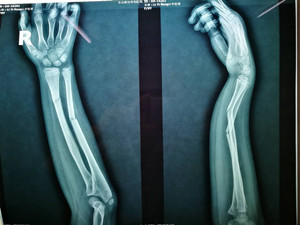

(整復(fù)前拍片)

看到女兒彎曲畸形的前臂,心疼不已的爸爸媽媽連忙抱起小女孩奔入附近的東港某骨科醫(yī)院。X線片顯示:左尺、橈骨骨折,骨折嚴(yán)重移位。這時(shí),媽媽首先想到的廣安醫(yī)院正骨科虞杰主任。之前,她曾在廣安醫(yī)院正骨科就診,對(duì)正骨科醫(yī)護(hù)人員的服務(wù)態(tài)度、服務(wù)質(zhì)量及醫(yī)療技術(shù)非常信任。